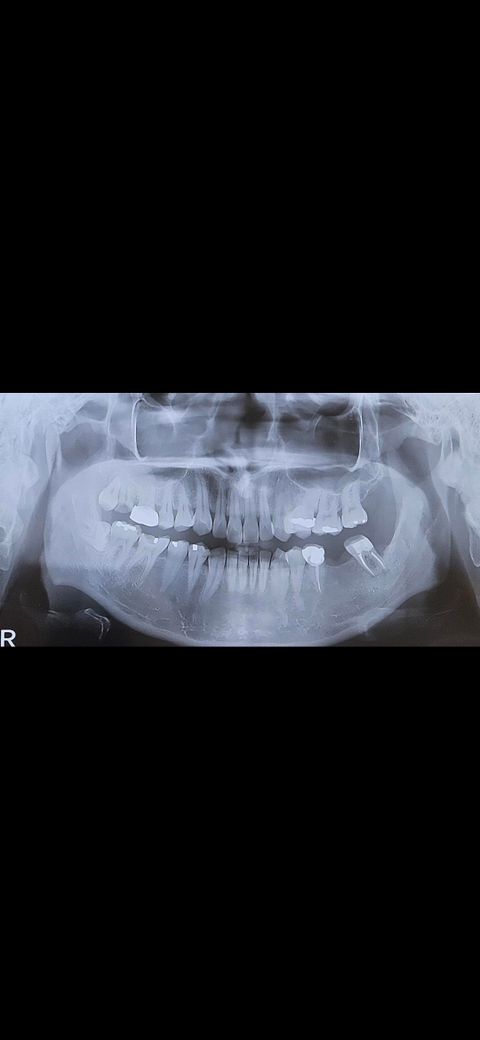

안녕하세요, 임플란트 가능할까요?

왼쪽부터 치료중입니다.

왼쪽 아래 어금니가 발치한지 오래되서

브릿지 해야한다는데..

임플란트는 어려울까요??

• 1번 째 사진

저정도면 임플란트 식립을 하셔도 될것같습니다. CT상에 문제가 잇는지 확인해봐야 겟지만 파노라마 상으로는 임플란트 하셔도 될것같아요.

사진으로만 봤을 경우에는 골밀도가 낮아 보입니다 하지만 임플란트를 못하는 정도는 아닐 것으로 생각됩니다 정확한 확인을 위해서는 치과에서 진료를 받아 보는 것이 좋습니다

각도가 안되면 임플란트를 심더라도 음식물이 계속 끼고 불편할 것입니다. 결손치 양쪽 치아를 일부 깍아내서 식립 각도를 형성해야 할 수도 있습니다. 현재 신경치료되어 있는 치아이기 때문에 깎더라도 시리지는 않겠으나 크라운을 씌워야 할 수는 있습니다.

어금니 발치한지 꽤 되어도 공간이 있으면 임플란트가 되지만 공간이 없으면 브릿지나 교정 후 임플란트 해야합니다.